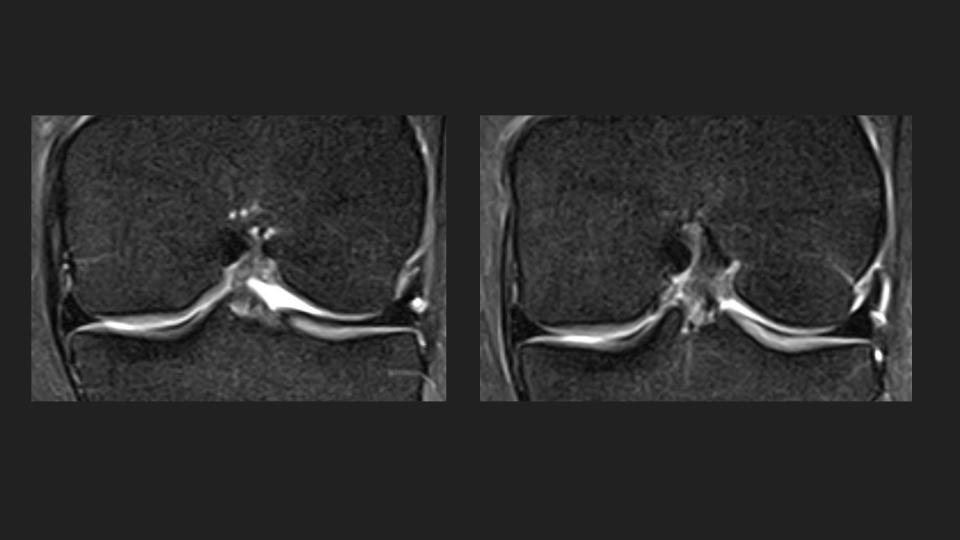

27M knee pain

This is an anteromedial meniscofemoral ligament. It looks alot like the relatively common ligamentum mucosum, but is is rare (approx 0.4% incidence) and inserts onto the central aspect of the anterior horn medial meniscus rather than the patella. It is eye-catching, but incidental and should not be resected. Reference article.

meniscofemoral ligament ( RID2806 )